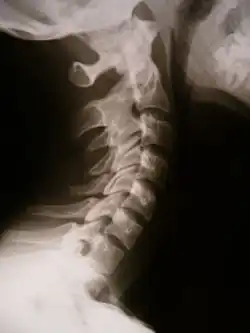

X-ray showing synostosis in the cervical spine